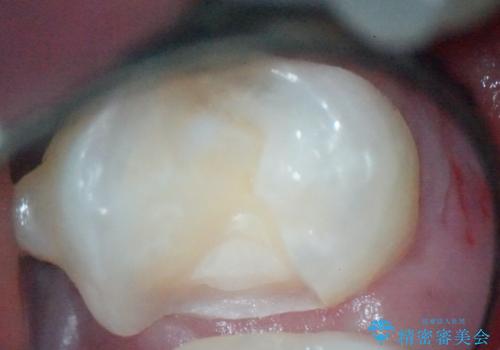

- 金属の詰め物を外して、セラミックインレーを入れたいと来院された患者様です。

奥歯に虫歯も認め、3歯の治療を来院回数2回で終了で終了しています。

当院でのセラミックインレーはすべてe-maxと呼ばれる高強度セラミックにて製作されます。

また、製作方法もプレスと呼ばれる方法を用いることで精度を高めています。